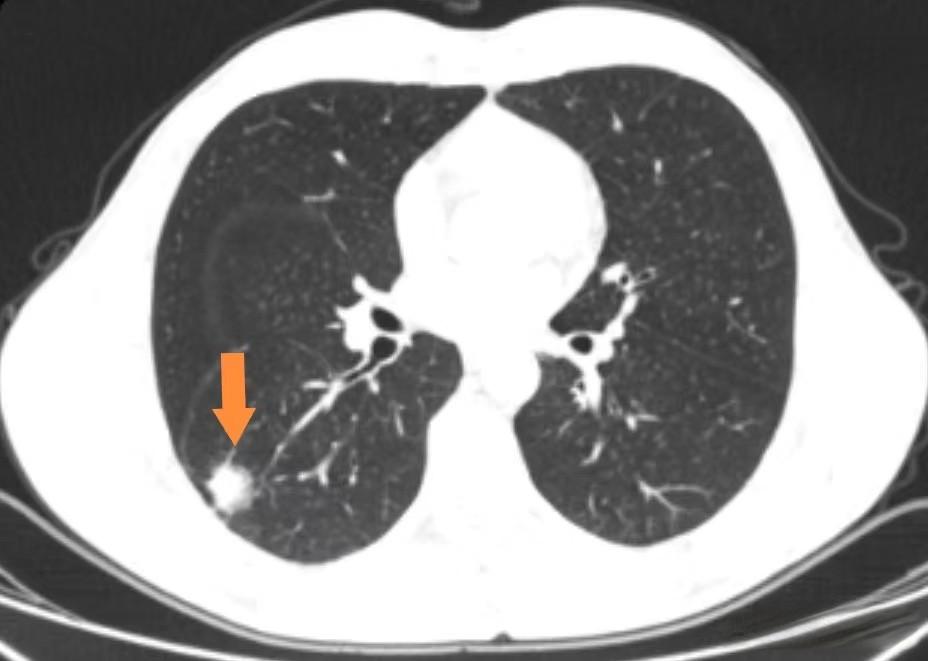

磨玻璃结节(GGO)是一种在CT影像上表现为密度轻度升高的肺部阴影,通常边界清晰。这种结节在早期肺癌筛查中较为常见,但大多数情况下是良性的。然而, 当磨玻璃结节中开始出现实性成分,形成所谓的部分实性结节时,其恶性潜能就显著增加了。

根据中国肺部结节分类、诊断与治疗指南(2016年版), 部分实性结节是指在CT影像上既有磨玻璃成分又有实性成分的肺结节。 这种结节的出现往往提示可能存在原位腺癌或微浸润性腺癌,这两种情况都需要密切监测或积极治疗。